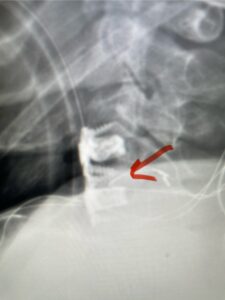

A 37-year-old male police officer complained of a one-month history of difficulty with his balance and leg weakness. He complained of achiness in his legs. He also complained of bilateral arm weakness and numbness of his hands. He was also having difficulty writing due to the weakness. Patient had an MRI of the cervical spine which demonstrated a disc/osteophyte at C56 causing spinal cord compression and concurrent myelomalacia (Fig. 3). Patient underwent an anterior cervical discectomy with a cage and plate (Fig. 4). He tolerated the procedure well with improved numbness and weakness. This is a young person with fairly extensive myelomalacia and a fairly rapid development of symptoms. For this it was felt surgery was indicated. How he will do will depend on how much of his symptoms was caused by the compressive component or intrinsic damage to the spinal cord. As a rule, patients generally improve to some extent quickly; but their recovery of their spinal cord function can sometimes take up to 2 years to realize the extent of their improvement. Patients have to be patient with themselves in terms of their expected recovery.

Fig. 4: Intraoperative lateral cervical x-ray demonstrating anterior cervical construct in good position at C 5 6 (red arrow)